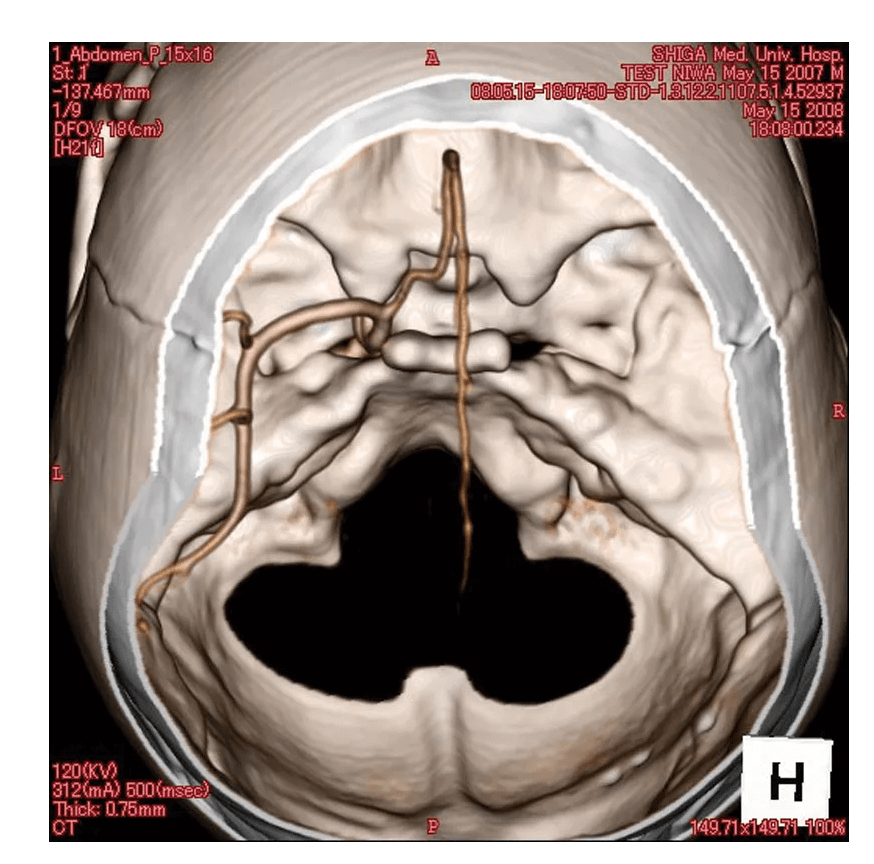

Das Angiographie Kopfmodell ist ein hochpräzises Trainingsmodell, das einen synthetischen Schädel in einen Kunststoffkopf integriert. In der linken Schädelhälfte sind die vordere und mittlere Hirnarterie nachgebildet und mit Kontrastmittel gefüllt, um realistische Trainingsbedingungen für die Angiographie zu schaffen. Die simulierten Arterien haben einen Durchmesser von 0,5 mm bis 4 mm und ermöglichen so eine detaillierte Untersuchung und Diagnose von Gefäßstrukturen im Gehirn. Dieses Modell ist besonders geeignet für medizinische Fachkräfte, die ihre Fähigkeiten in der Angiographie und Bildgebung von Gehirngefäßen verbessern möchten.

Präzise Nachbildung der vorderen und mittleren Hirnarterien im synthetischen Schädel

Arterien mit Durchmessern von 0,5 mm bis 4 mm für detaillierte Bildgebungstraining

Mit Kontrastmittel gefüllte Arterien ermöglichen realistische Angiographie-Simulationen